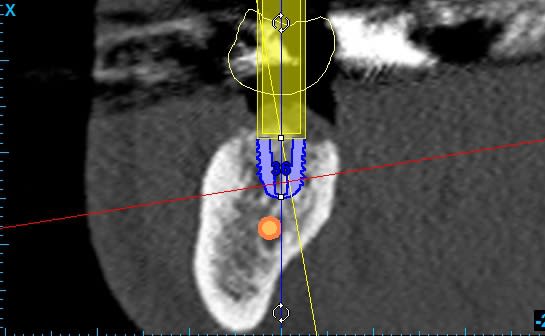

Sur la simulation que je joins, j'ai placé 2 implants 5.2 x 6.5 pour 36 et 46 en unitaire.

"quelle distance as tu entre l'implant et le NAI?"

> 2 mm. Je ne peux pas aller plus bas.